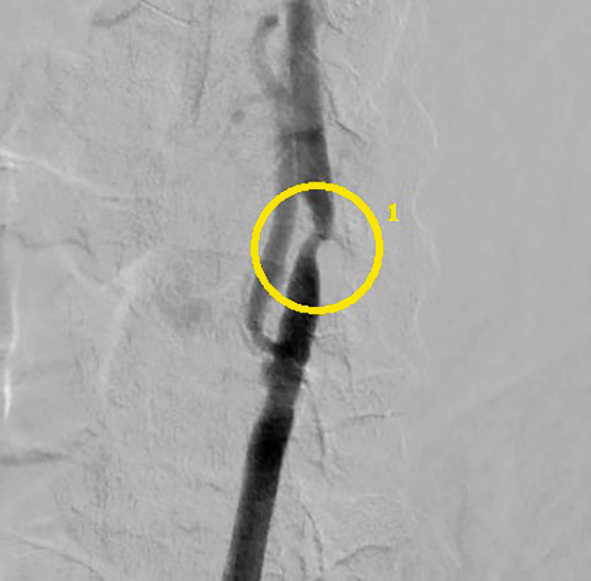

Перед вмешательством больной получил нагрузочную дозу клопидогреля (300 мг). Первым этапом в эндоваскулярной операционной выполнялось ЧКВ ПНА. Введено 10 тыс. ЕД гепарина внутриартериально. Через трансфеморальный доступ справа (интродьюсер 6F, катетер 6F) был установлен стент с лекарственным покрытием «Endeavor Resolut» («Medtronic», США) (рис. 5). Далее через тот же доступ (катетер 6F) с использованием дистальной защиты («Filter Wire EZ», «Boston Scientific Corporation») проведена каротидная ангиопластика со стентированием левой ВСА, установлен стент «RX Acculink» («Abbot Vascular») (рис. 6). После завершения процедуры больной был транспортирован в сосудистую операционную. Время между ангиопластикой и началом КЭЭ составило 30 мин. Под эндотрахеальным наркозом (введено дополнительно 5 тыс. ЕД перед пережатием ВСА) выполнена классическая КЭЭ справа с пластикой зоны реконструкции заплатой из диэпокси- обработанного ксеноперикарда. Время пережатия артерий составило 25 мин. Послеоперационный период протекал без особенностей. Клиника стенокардии не рецидивировала. По данным цветного дуплексного сканирования брахиоцефальных артерий признаков рестеноза, увеличения скоростных показателей в ВСА с 2 сторон не определяется. Пациент выписан на 7-е сутки после операции в удовлетворительном состоянии. Рекомендован приём двойной дезагрегантной терапии (клопидогрель 75 мг + ацетилсалициловая кислота 125 мг).

Рис. 5. Стентирование передней нисходящей артерии: 1 — установленный стент. / Fig. 5. Left anterior descending artery stenting: 1 — installed stent.